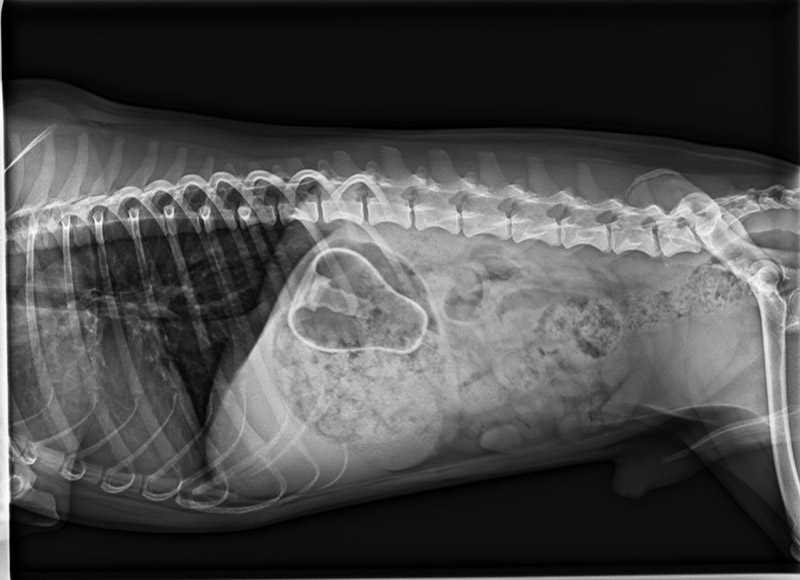

Luis und die verflixte Birne

Pflegehund Luis hatte richtig Pech. Leider hatte er seine Quitschiebirne zum Fressen gerne. Diese hing im Magen fest, sodass eine Notfalloperation durchgeführt werden musste.

Zum Glück ist alles gutgegangen. Dem kleinen quirligen Mann geht es wieder gut.

Aber es gab natürlich auch eine Rechnung über 1000 Euro, die ein Loch in unsere Kasse gerissen hat. Also bitte seid vorsichtig, von diesen weichen Spielzeugen raten wir dringend ab. Eine gute Alternative sind die Vollgummispielzeuge von Kong, sie sind nahezu unverwüstlich. Spielzeug sollte natürlich auch nur unter Aufsicht benutzt werden, aber das entspricht meist nicht dem praktischen Alltag. Also lieber hochwertiges Spielzeug kaufen und möglichst die Augen offen haben.